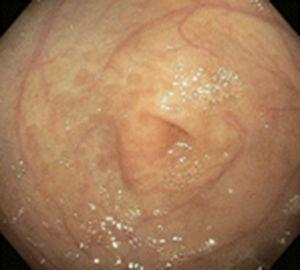

Existen varios estudios en relación con los hallazgos tanto endoscópicos como histológicos que se presentan en los niños con APLV, y de los primeros los más frecuentemente reportados son eritema focal, erosiones e hiperplasia nodular linfoide (fig. 1); estas alteraciones se presentan en un 40-90% de los casos28,29. Respecto a los hallazgos histológicos de las biopsias esofágicas, gástricas, duodenales y rectales, la gran mayoría de los autores está de acuerdo en que la presencia de más de 60 eosinófilos en 6 CAP y/o más de 15-20 por campo es muy sugestivo de APLV (fig. 2), a pesar de que existen algunos informes en la literatura en los cuales hacen referencia a que 6-10 eosinófilos/CAP puede ser sugestiva de esta dolencia29.

En estos 2 grupos de pacientes estudiados, en 52 (44.8%) se encontraron estos hallazgos (más de 60 eosinófilos por 6 CAP y/o más de 15 eosinófilos por campo) en las biopsias siendo el rectosigmoides el sitio más afectado (31 pacientes), duodeno (12 pacientes), antro 2 casos y esófago un caso (tabla 3). Mientras que las alteraciones endoscópicas solo se presentaron en el 33% de los casos y fueron eritema focal, erosiones y únicamente en 3 hiperplasia nodular linfoide. Esto contrasta con lo publicado por otros autores a nivel mundial como Goldman y Antonioli27 los cuales, en un estudio de 20 pacientes con proctocolitis por APLV, reportaron que los hallazgos macroscópicos durante la rectosigmoidoscopia fueron áreas de eritema focal e hiperplasia nodular en el 95% y en el 60% los hallazgos histológicos característicos de más de 15 eosinófilos por CAP; y difiere también con lo publicado por Hwang et al., los cuales en 38 pacientes con proctocolitis alérgica encontraron anormalidades endoscópicas en todos los pacientes, hiperplasia nodular linfoide en el 94.7% y eritema focal en el 5.3%, mientras que los hallazgos histológicos en todos los casos fue de más de 60 eosinófilos en la lámina propia en 10 CAP30. Todo esto puede ser explicado en base a la edad de nuestros pacientes que fueron menores de 13 meses, y como es de esperarse, a mayor edad se incrementa el daño de la mucosa intestinal y por lo tanto el eritema focal y la hiperplasia nodular.